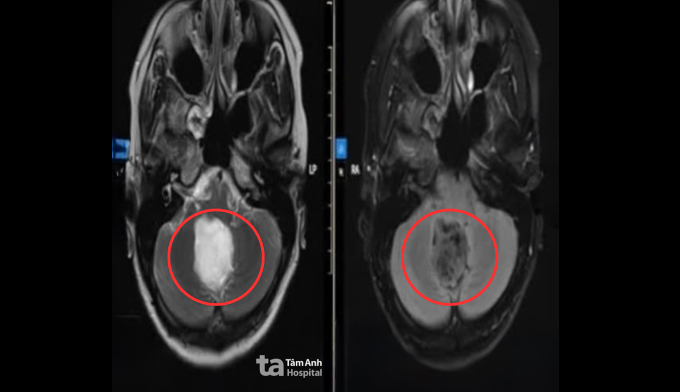

Triệu chứng của chị Trang xuất hiện vài tháng trước, thi thoảng có cảm giác như điện giật ở gáy, sau tai, đôi khi lan lên đỉnh đầu. Cơn đau đến rồi tự hết nên chị nghĩ do mệt mỏi căng thẳng, đến khi đau đầu dữ dội, yếu nhẹ tay trái và tâm trạng bồn chồn, lo lắng khó giải thích, chị mới đến Bệnh viện Đa khoa Tâm Anh TP HCM. Kết quả chụp MRI 3 Tesla cho thấy một u nang kích thước khoảng 4 cm ở vùng lỗ Magendie, hố sau, nằm sát thân não. U nang đã chèn ép thùy nhộng tiểu não và mặt sau thân não, làm hẹp đường lưu thông dịch não tủy, gây giãn nhẹ hệ thống não thất.

Sau phẫu thuật, chị Trang tỉnh táo, tiếp xúc tốt, sức cơ tay trái cải thiện. Ảnh CT sọ não hậu phẫu cho thấy các cấu trúc não trở về vị trí bình thường, tụ khí và dịch trong hố sau lượng ít. Một tuần sau mổ, người bệnh ổn định, lưu viện theo dõi và bắt đầu tập vật lý trị liệu, phục hồi chức năng. Dự kiến sau khoảng ba tuần, chị có thể trở lại sinh hoạt bình thường và được tái khám định kỳ để theo dõi nguy cơ tái phát u.